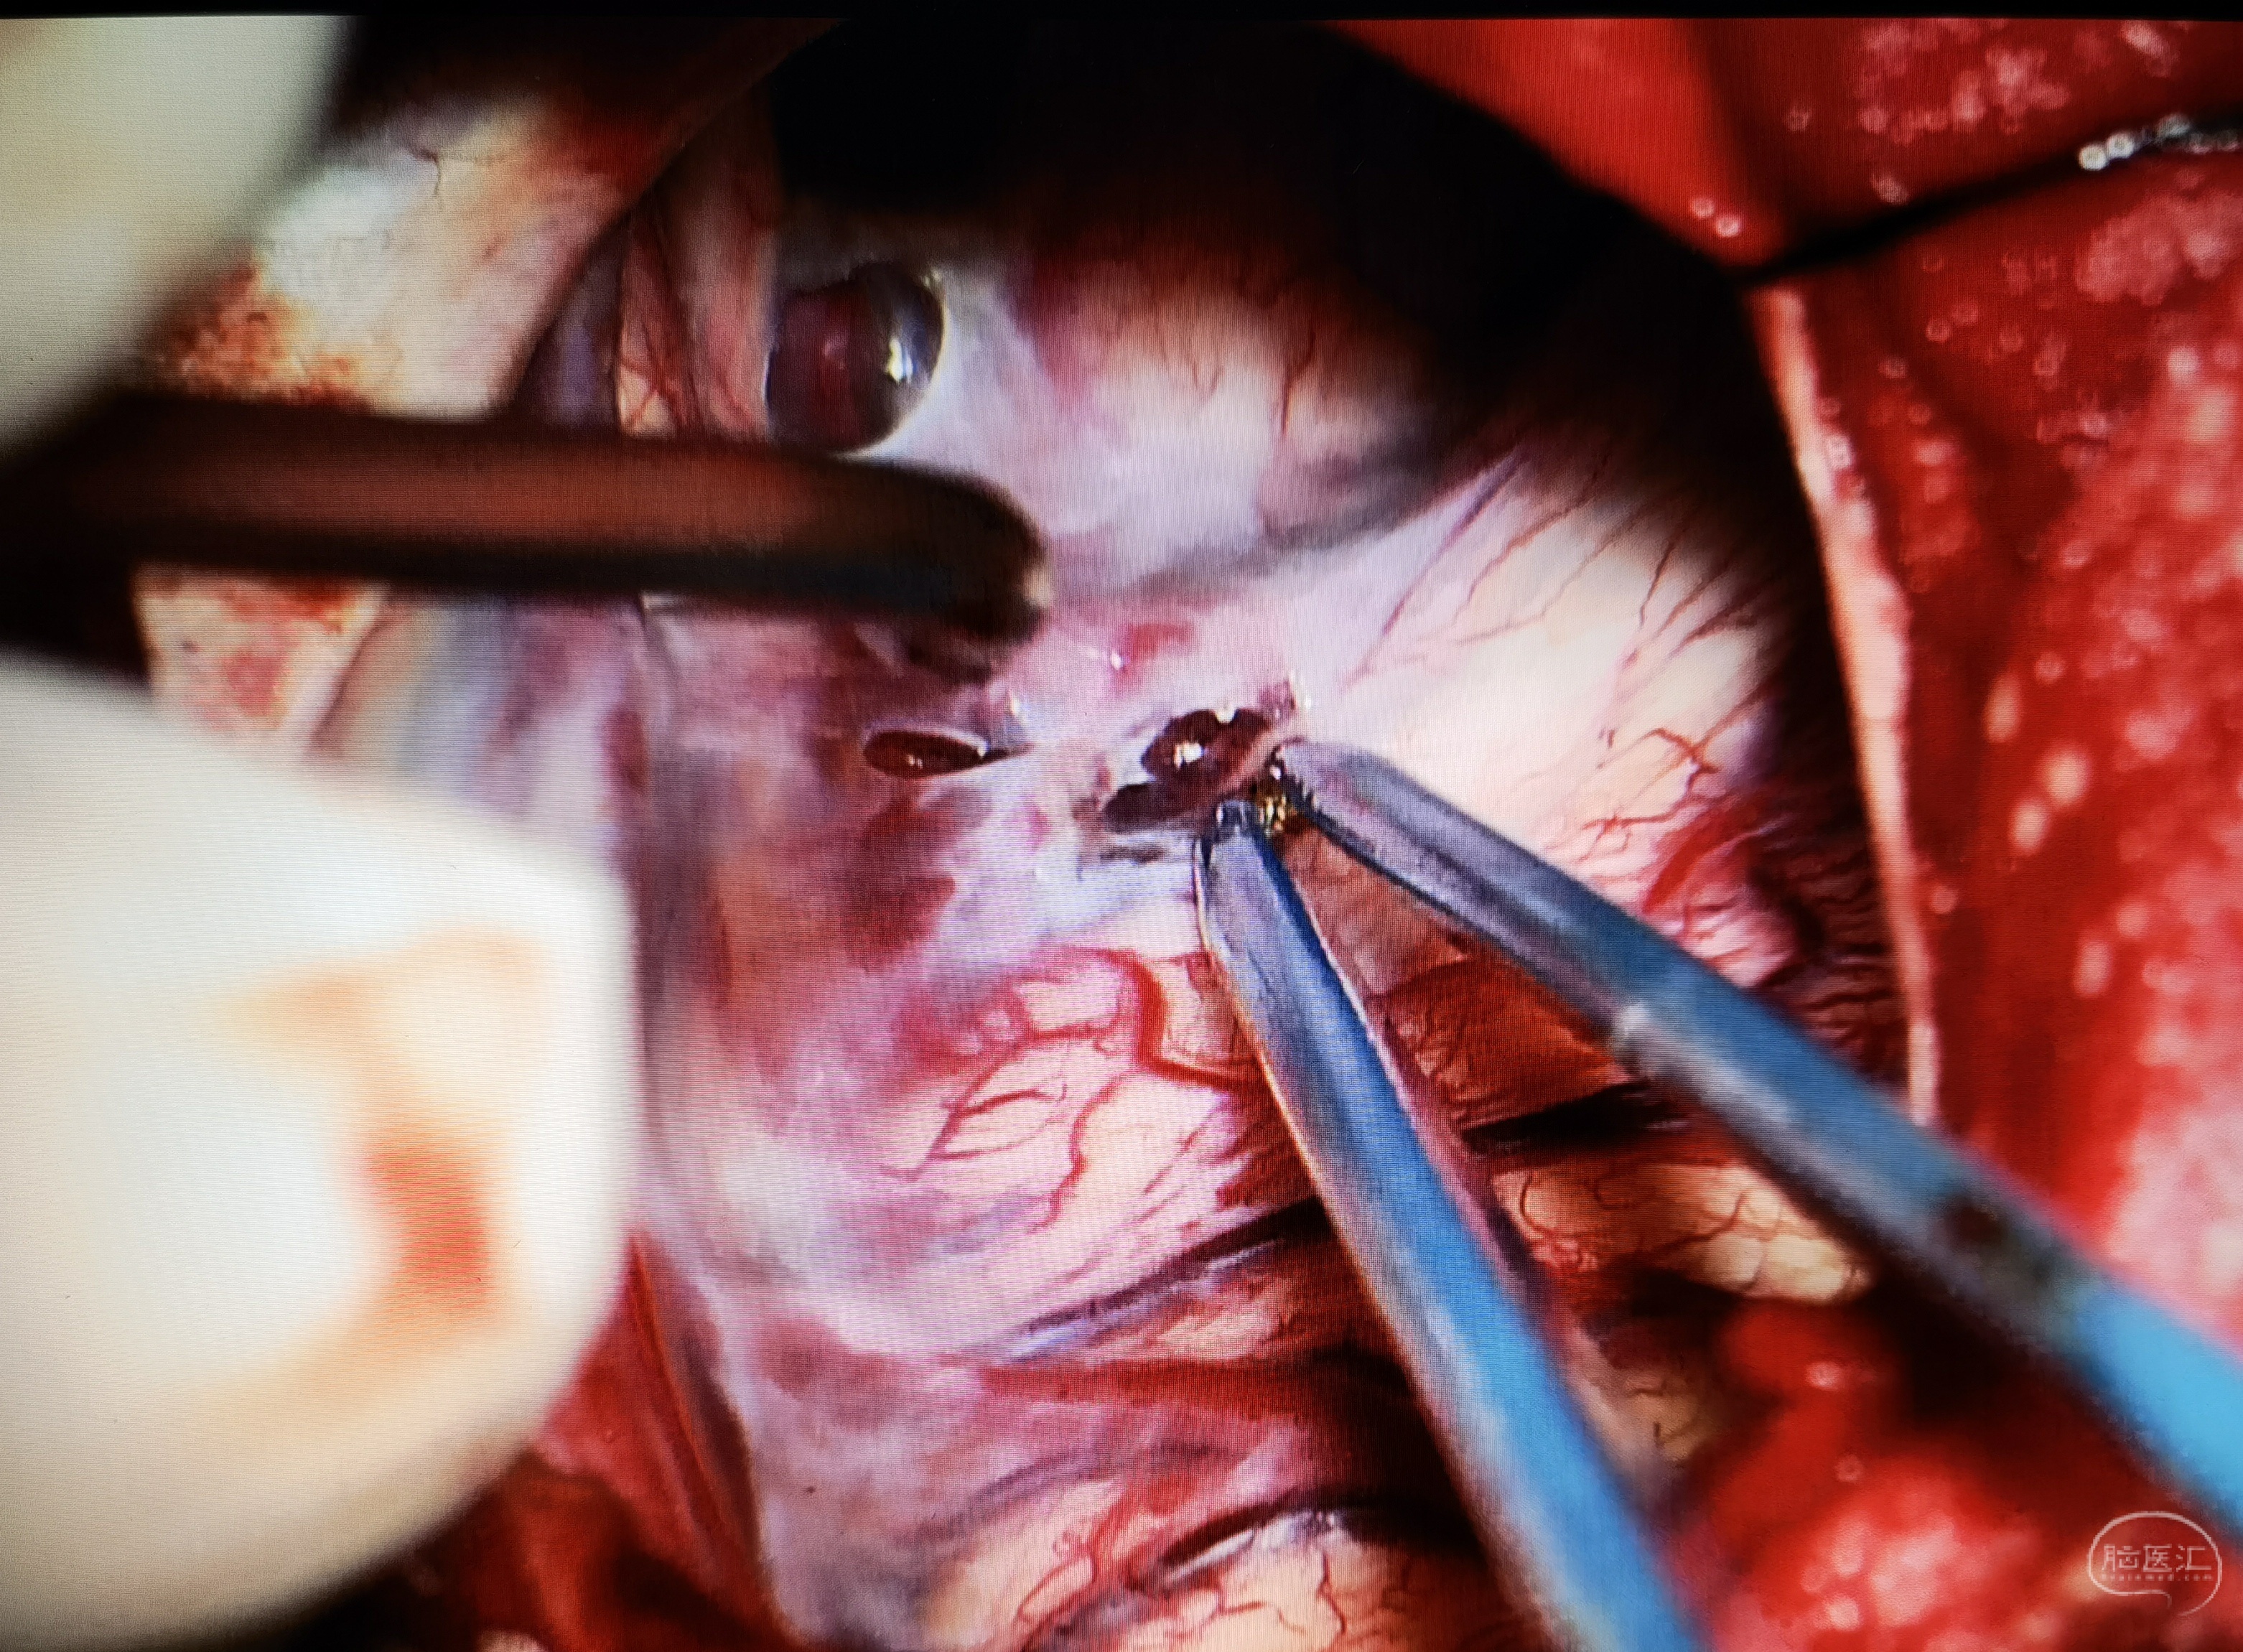

考虑到患儿囊肿体积巨大,占位效应明显,向患儿家属交代病情及手术风险后,行小骨窗开颅蛛网膜囊肿-脑池造瘘术,术中打通侧裂池、颈动脉池、基底池,多处造瘘,瘘口大小为1-1.5cm,并切除部分囊壁。术后患儿无新发症状,病情恢复良好,定期复查随访。

术中造瘘